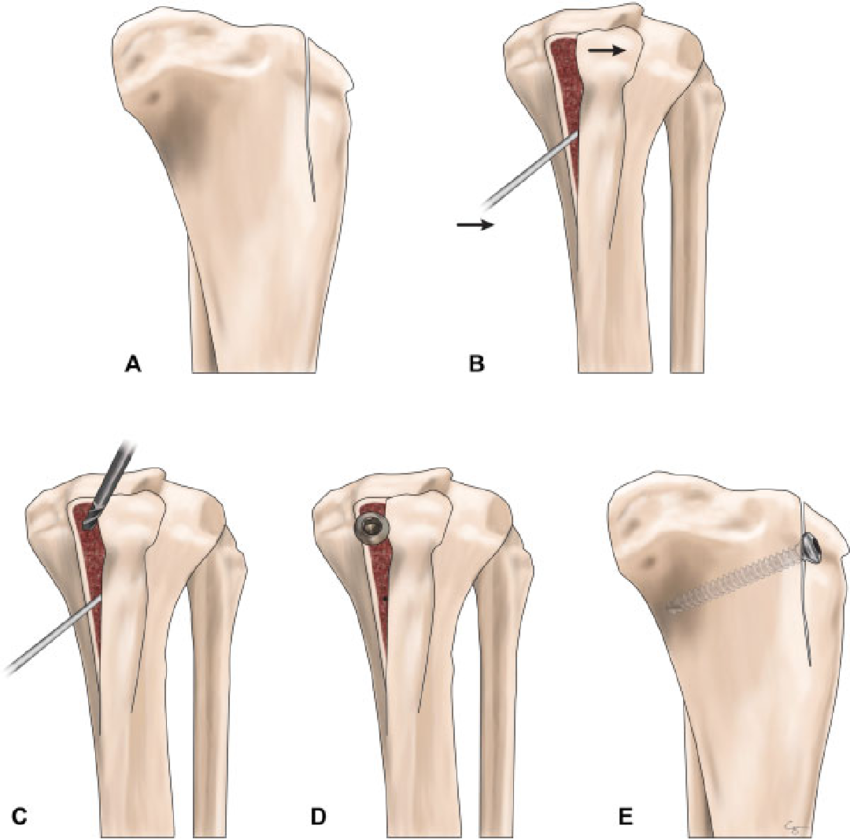

Sulkoplasti

Patellanın kaydığı oluktan blok bir parçanın kesilerek altının derinleştirilmesi ve bu kıkırdak bloğun yerine tekrar yerlleştirilmesi ile derinleşmiş bir oluk elde etme prensibine dayanır.